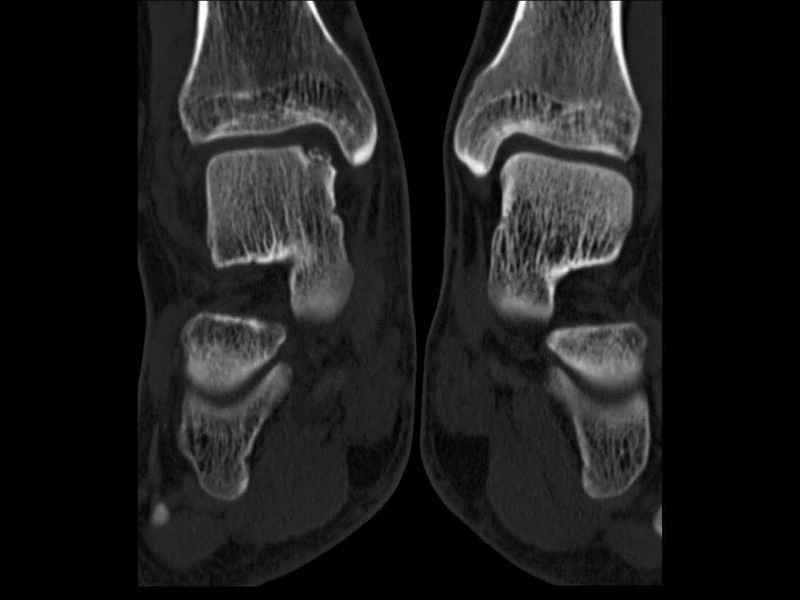

Уважаемые коллеги, обратился за помощью пациент, мужчина, 25 лет. С жалобами на болевой синдром в области голеностопного сустава и среднем отделе стопы. Травму отрицает. Со слов, болевой синдром в течении 1 года. Последние 1-1.5 мес периодически вынужден пользоваться костылями. После ограничения нагрузки боли уменьшаются.Соматически здоров. До появления болей активно занимался рукопашным боем. На СКТ картина рассекающего остеохондрита блока таранной кости, киста шейки таранной кости с признаками импрессии суставной поверхности. А также - разрастания переднего края б\берцовой кости сопровождающиеся клиникой импиджмент синдрома. Предполагаемый план лечения- удаление свободного фрагмента суставного хряща из трансмаллеолярного доступа с рассверливанием поверхности дефекта, кюретаж кисты шейки с заполнением полости биокомпозитом + дебридмент переднего отдела голеностопного сустава. Прошу высказать своё мнение, за и против, предполагаемого плана лечения. А также по возможности ответить на вопросы: 1. Есть ли необходимость в улучшении васкуляризации таранной кости (например подтаранный артродез). 2. Учитывая планируемое применение биокомпозитного цемента целесообразно ли заполнение им дефекта блока таранной кости с моделированием края суставной поверхности.

СТ чётко демонстрирует секвестр, но открыв сустав вероятно, что хрящ тарана окажется интактным и только пальпацией/ ЭОП можно будет

идентифицировать локализацию секвестра. Если вы с этим столкнетесь, то секвестрэктомию я бы предложил сделать не со стороны суставной поверхности тарана, а со стороны угла тарана, субхондрально кюрретаж стенок, разнонаправленную туннелизацию спицей или 1.1мм сверлом и заполнить дефект спонгиозным графтом.

- Резекция экзостоза переднего края б.б. кости